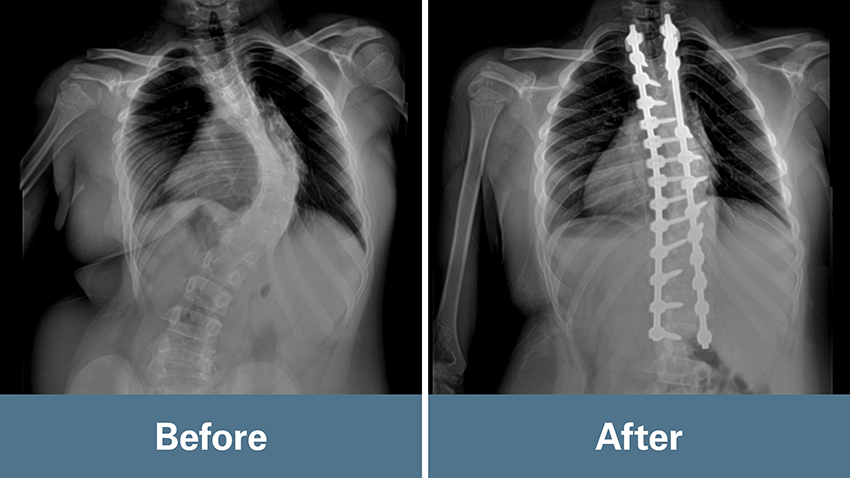

On their first appointment in January 2024, Mundluru noted Louis had a significant curve approaching 80 degrees that had progressed over time. His scoliosis was uncompensated, meaning his body had shifted to one side relative to his pelvis.

In May 2024, Mundluru performed a posterior spinal instrumented fusion (PSIF) to correct Louis’ spine. He dissected the spine to the appropriate level using X-ray guidance. Spine image navigation helped ensure the accurate placement of screws. A rod was manually contoured for certain parameters to aid in a precise fit while still correcting the spine to a safe and desirable position.

“You don’t want to straighten the spine too much, because that can be dangerous. The nerves and spinal cord can’t take it, so you look for that happy, safe medium,” he said.

“We often have to troubleshoot. We had to do some extra steps to loosen Louis’ spine, which added a little more risk,” Mundluru said. “But the risk was worth the reward because he really responded well. That’s why we were able to get the correction that we did.”

In Louis’ case, they achieved almost an 80%-85% correction — despite it being a challenging case. The results were well beyond the 50% correction Mundluru had prepared the family to expect because of the rigidity of his curve.